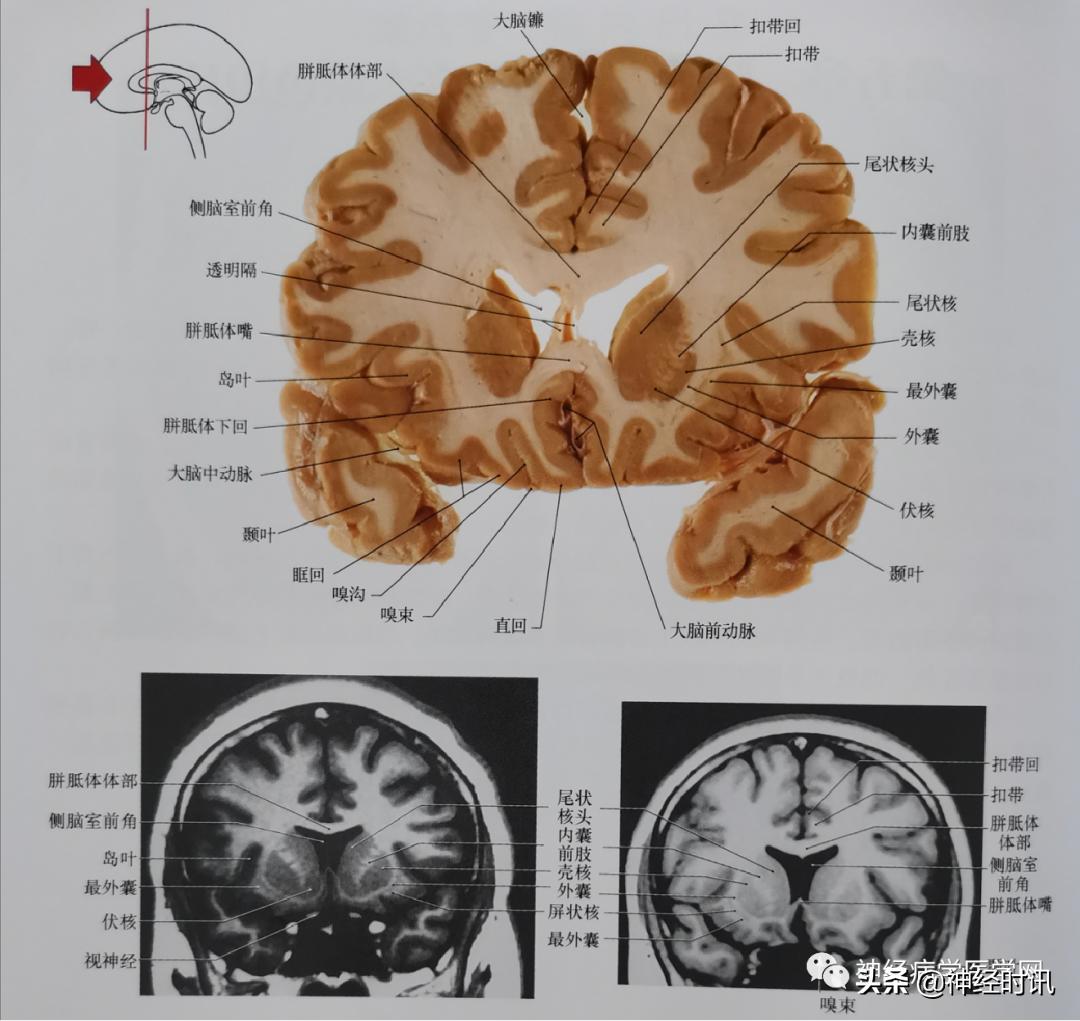

熟悉断层解剖重要,掌握断层解剖与影像结合更重要。

图1 通过内囊前肢及尾状核头平面的冠状位嘴侧面影像。尾状核头在此冠状位平面显示非常清楚。亨廷顿病(一种遗传性的神经系统退行性疾病)的病人,尾状核头部可完全消失,侧脑室前角在此水平显著扩大。这两张片子为相同平面磁共振影像(均为反转恢复技术),可显示许多切片上确认的解剖结构。